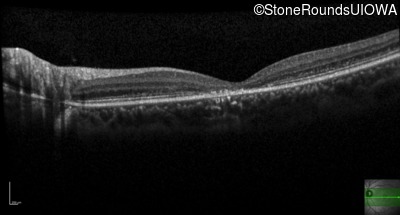

Age at visit: 17 years

Age at visit: 19 years

Age at visit: 20 years

Age at visit: 21 years

The clinical features favoring the diagnosis of ABCA4-associated autosomal recessive Stargardt disease include: loss of acuity in the second decade, reduction in color discrimination and foveal photoreceptor loss on OCT.